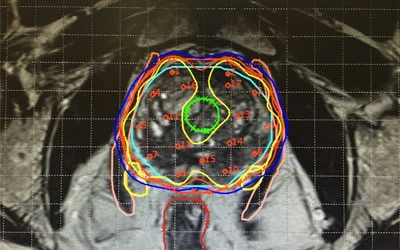

3D brachytherapy is an advanced medical technique employed in the treatment of various cancers, particularly prostate cancer and gynecological malignancies. Unlike traditional brachytherapy, which relies on two-dimensional imaging, 3D brachytherapy utilizes three-dimensional imaging technology, such as CT or MRI scans, to precisely target cancerous tissues while minimizing damage to surrounding healthy tissue. This approach allows for more accurate placement of radiation sources directly into the tumor, resulting in higher treatment efficacy and reduced side effects. By customizing the radiation dose based on the tumor’s specific size, shape, and location, 3D brachytherapy offers patients a tailored and effective treatment option, often leading to improved outcomes and better quality of life.

3D brachytherapy revolutionizes cancer treatment by combining precision targeting with advanced imaging technology. Unlike traditional methods, it utilizes detailed three-dimensional models of tumors and surrounding tissues, allowing oncologists to tailor treatment plans to each patient’s unique anatomy. This approach minimizes radiation exposure to healthy tissues, reducing side effects and improving outcomes. With enhanced dose delivery and real-time monitoring, 3D brachytherapy ensures patient safety while expanding treatment options for a wide range of cancers, from prostate to gynecological. Its ability to deliver precise radiation doses directly to tumors makes it a valuable tool in the fight against cancer, offering hope and improved quality of life for patients.